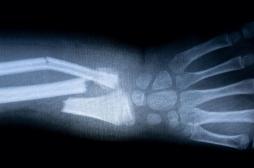

J ai Mal Bras et mains Bras et mains Tête et cou Torse et haut du dos Jambes et pied